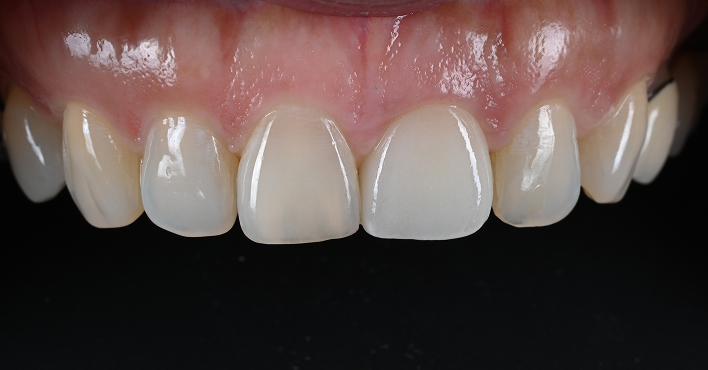

리봄치과의 임상증례 공개는 자신감입니다.

BEFORE & AFTER

01임플란트2023.06.02 - 2025.03.26

BeforeAfter

02임플란트2023.08.16 - 2024.07.16

03임플란트2020.10.12 - 2021.08.30

04임플란트2020.08.17 - 2021.05.24

05임플란트2020.10.24 - 2021.08.10

06임플란트2020.04.17 - 2021.01.15